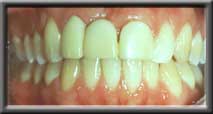

Severe ridge defect after extraction |

Ridge augmented to return normal shape |